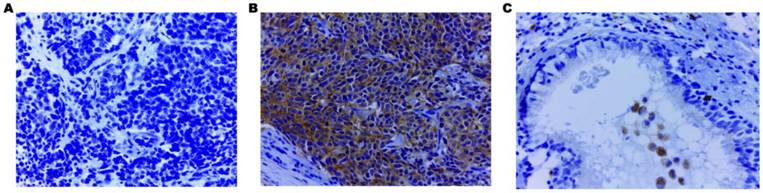

Using IHC, EHD1 protein expression was examined in tumor, lymph node metastases and normal bronchial epithelial tissues of 85 SCLC patients. The frequency of positive staining for EHD1 was 58.82%(50/85) in the SCLC samples, which was significantly higher (P < 0.001) than that in the normal tissues(21.18%) (Table 1). The cytoplasmic staining patterns observed for EHD1 were consistent with data from our previous studies (Fig. 1) [26, 27].

Fig 1

Immunohistochemical staining of EHD1 in FFPE tissue samples (×400). (A) Cytoplasmic EHD1-negative specimen (SCLC). (B) Cytoplasmic EHD1 high-expression specimen (SCLC). (C) Cytoplasmic EHD1 low-expression specimen (normal bronchial epithelial tissue).